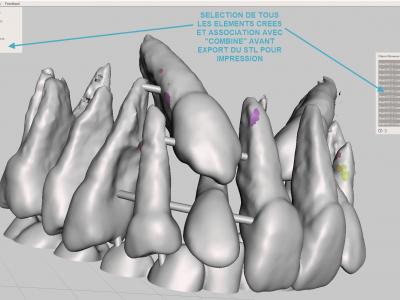

- Etape de solidarisation : si certaines dents ne sont pas en contact avec d'autres, les solidariser avec l'adjonction de cylindres, puis fusionner les éléments avec l'outil "combine"

- Exporter le fichier STL à imprimer